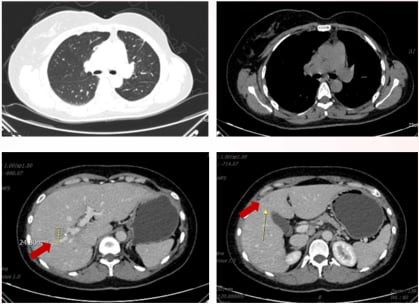

5. 第四次复发与小分子靶向药(2024)

2024年9月,患者再次出现疾病进展,肝门部及S4段转移灶较前增大。MDT后,患者接受了吡咯替尼+卡培他滨的治疗方案。吡咯替尼是一种口服的小分子酪氨酸激酶抑制剂(TKI),能够同时抑制HER1、HER2和HER4,阻断癌细胞的信号通路。卡培他滨则是一种口服化疗药物。此方案胃肠道反应I级,骨转移继续给予唑来膦酸和补钙治疗。